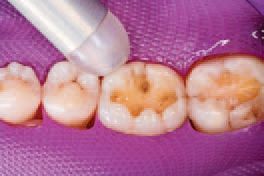

After inspecting the old amalgam restorations (Fig. 2), a rubber dam was then placed (Fig. 3). Next, using Sybron Dental’s Axis course diamond bur, KS3, the amalgam restorations and all damaged tooth structure were removed (Fig. 4).